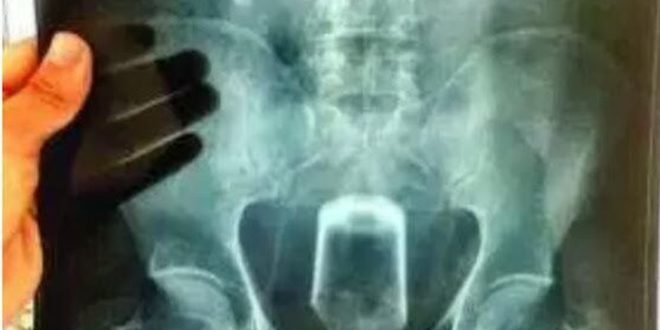

No Raios X é possível vê a posição do copo dentro do jovem, que não teve seu nome revelado.

Um suposto homossexual deu entrada na noite desse sábado (7) no Hospital Estadual de Emergência e Trauma ‘Senador Humberto Lucena’ para retirar um copo do ânus.

De acordo com informações, o fato bizarro, ocorreu no bairro de Cruz das Armas, quando rapaz, propositalmente, introduziu um copo no orifício. “Ele lubricou o copo com óleo de comida e sentou em cima”, disseram.

Com a pressão, o copo teria entrado. Ele foi socorrido inicialmente para a Unidade de Pronto Atendimento do bairro, sendo transferido para o Hospital de Trauma.